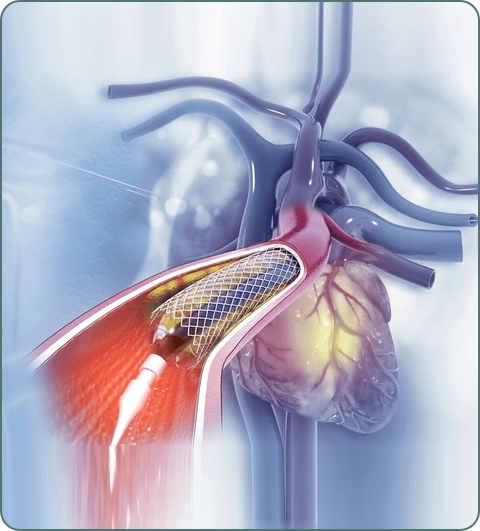

Percutaneous Coronary Intervention (PCI)

Balloon angioplasty and stenting to open blocked coronary arteries. Minimally invasive procedure for treating heart attacks and angina.

Primary Angioplasty

Emergency PCI for heart attacks. Fastest and most effective treatment for ST-elevation myocardial infarction (STEMI).